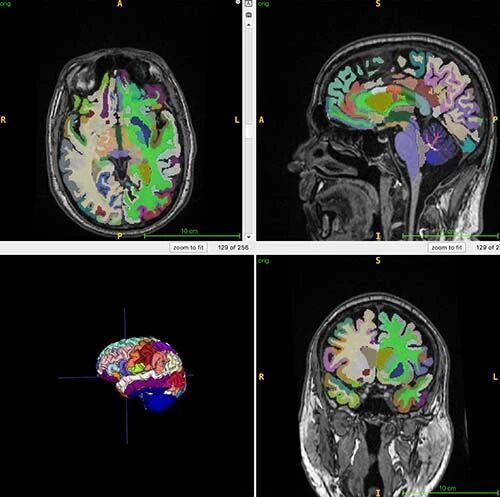

这项研究已经招募了4个地点,共1164名健康个体接受了全身核磁共振成像(MRI),参与者的平均年龄为55.17岁。在本研究中,研究人员使用T1加权扫描模式,这种方式可以让脂肪在最终的扫描成像中呈亮色,而液体呈暗色,从而能更好地区分肌肉、脂肪和脑组织。同时,研究人员使用人工智能算法来量化肌肉体积、内脏脂肪、皮下脂肪和大脑年龄。

在本研究中,研究人员使用脑部MRI结合人工智能量化脑部年龄。图片来源:RSNA.org/press25